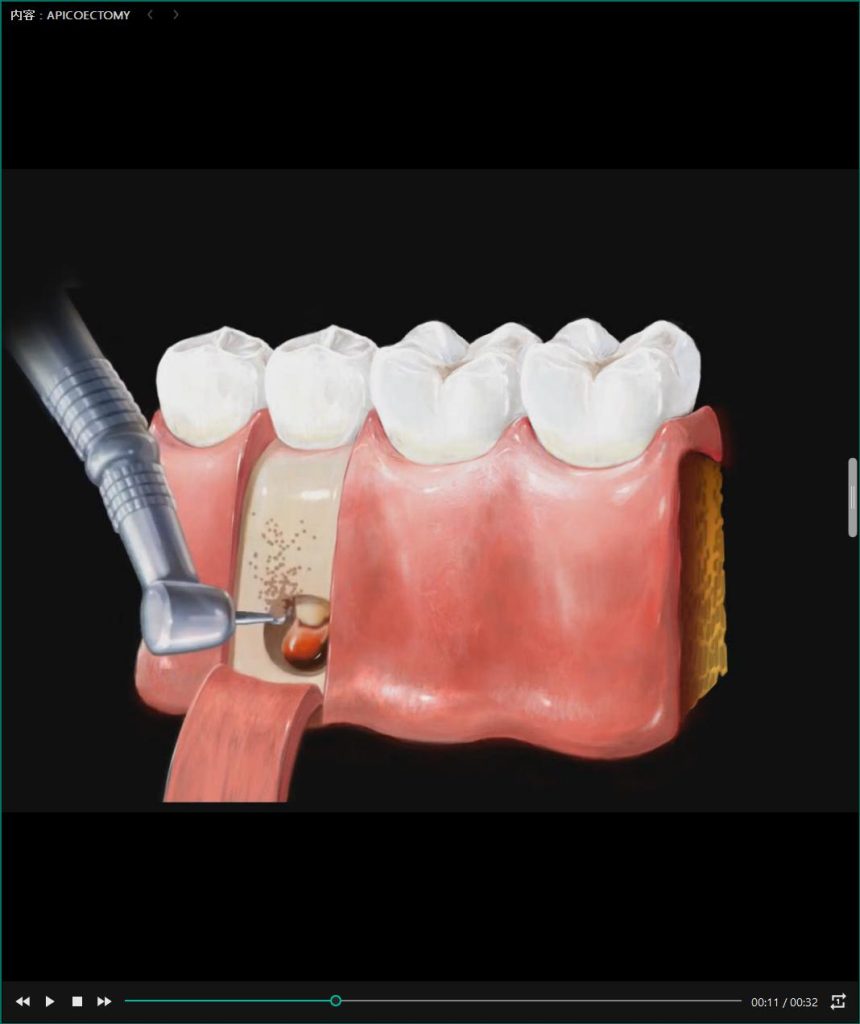

また、経営面においては、260種類以上の治療説明用動画を標準搭載している点も大きな強みだ。「撮影した高精細な画像と動画を並べて見せることで、患者様の納得感が劇的に高まり、自費診療の同意率向上に直結します。他社では高額なオプションとなることが多い機能を、私たちはあえて基本機能として提供しています」